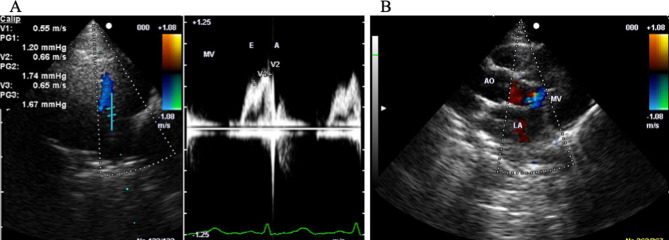

非人类灵长类动物的自发性心脏病为人类心脏病提供了一个有用的模型。然而,诊断心脏病通常需要专门的技术,如超声检查。这项研究的重点是心脏激素,它可以通过血液检查来检测心脏病。我们测量了健康的年轻日本猕猴(Macaca fuscata)在室内单独饲养的心房钠肽(ANP)和脑钠肽(BNP)的浓度,在胸部x光片、心电图、超声心动图、全血细胞计数和血清生化测试中没有异常,以建立参考值。本研究中使用的猴子包括29只雄性(28-47个月)和29只雌性(22-65个月)。采用免疫放射测定法测定ANP水平。化学发光酶免疫分析法检测脑钠肽水平。58只日本猕猴平均ANP水平为25.7±9.6 pg/mL, 29只雄性猕猴平均ANP水平为26.7±9.6 pg/mL, 29只雌性猕猴平均ANP水平为24.7±9.5 pg/mL。性别间无显著差异。ANP与年龄之间没有相关性,但被排除在外的猴子的结果超出了这些范围。研究人员还对58只猴子进行了BNP检测,其中22只猴子的BNP水平低于检测下限(

Spontaneous cardiac disease in nonhuman primates offers a useful model of human cardiac disease. However, diagnosing heart disease generally requires specialized techniques such as ultrasonography. This study focused on cardiac hormones that can be used to detect cardiac disease from blood tests. We measured concentrations of atrial natriuretic peptide (ANP) and brain natriuretic peptide (BNP) in healthy young Japanese macaques (Macaca fuscata) housed individually indoors, with no abnormalities in thoracic X-rays, electrocardiograms, echocardiograms, or complete blood counts and serum biochemistry tests, to establish reference values. The monkeys used in this study comprised 29 males (28-47 months old) and 29 females (22-65 months old). ANP levels were determined by immunoradiometric assay. BNP levels were determined by chemiluminescent enzyme immunoassay. Mean ANP level was 25.7 ± 9.6 pg/mL for all 58 Japanese macaques, 26.7 ± 9.6 pg/mL for the 29 males, and 24.7 ± 9.5 pg/mL for the 29 females. No significant difference was identified between sexes. No correlation was seen between ANP and age but excluded monkeys showed result of outside these range. BNP was also measured, with 22 of the 58 monkeys showing levels below the lower limit of detection (<4.0 pg/mL). Taking levels in these 22 animals as 4.0 pg/mL, mean BNP level was 5.1 ± 1.6 pg/mL and BNP elevated in two excluded monkeys. These results establish mean values for cardiac hormones in young Japanese macaques. These standards may provide useful indicators for the early detection of cardiac disease in animal models.